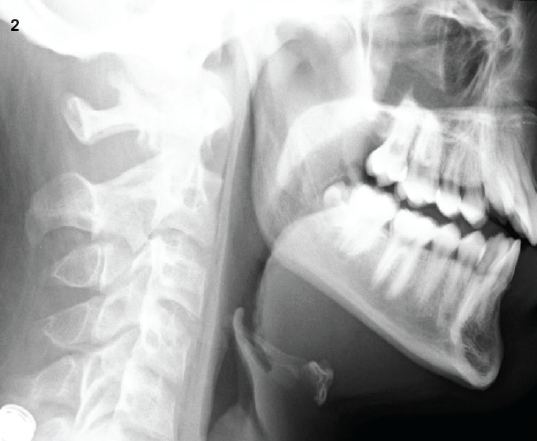

Pneumomediastinum

11/12/2013

John Bishara, DO; Thomas O'Donnell, MD; Catherine Caronia, MD; Rajesh Savargaonkar, MD

A 16-year-old boy presented to the pediatric emergency department with a 1-day history of progressively worsening neck and chest pain.